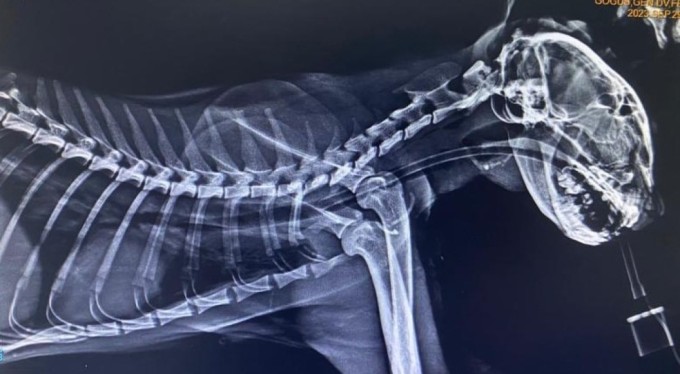

Veteriner hekime getirilen sokak kedisinin röntgeninde boğazına saplanmış üç tane olta kancası olduğu tespit edildi. Ameliyata alınan kedinin boğazındaki kancalar çıkartıldı. Yaklaşık bir saat süren ameliyatta kancaların derine saplandığı görüldü. Ameliyattan sonra kedi sağlığına kavuşurken veteriner hekim Furkan Alkan, süreci şöyle aktardı:

"Vaka geldiği zaman ağzında salya akıntısı ile geldi. Üç günden beri bu haldeymiş. İlk yaptığımız muayenede kancanın bir kısmını gördük ve hemen röntgeni çektik. Röntgende 3 tane kancanın boğazına takıldığını gördük. Endoskopi yardımıyla 3'ünü birden çıkardık. Üçü de çok derine saplanmıştı. Yarım saat bir saatlik bir operasyonla arkadaş sağlığına kavuştu. Ya balık alırken ya da balıkçılar tarafından atılan balığı kaparken kancayla beraber kaptı. Kancaları yuttu. Oraya saplandığı için de ne ağızda kaldı ne de mideye gitti. 3-4 günden beri enfeksiyonlu ağız akıntısı varmış, kliniğimize gelip tedavisini gördü. 4-5 yaşlarında sokak hayvanı. Bir hayvansever tarafından getirildi. Masraflarını hayvansever karşılıyor."